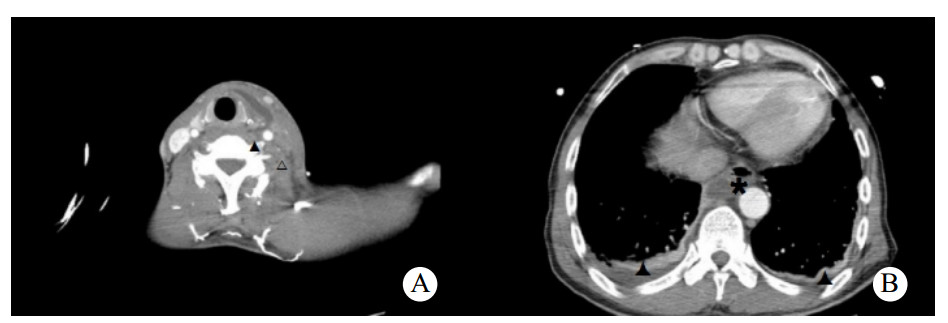

患者男,50岁,因“进行性左侧咽痛6 d”于2019年4月30日入院。患者6 d出现左侧牙痛、咽痛,伴发热(体温不详),未予治疗。3 d前咽痛加重,遂至当地医院就诊,CT提示左侧咽旁软组织肿胀伴喉腔变窄,超声提示左侧颌下腺炎,予以头孢米诺钠抗感染治疗后咽痛无好转,并出现呼吸困难及胸闷,左侧颈部肿痛。10 h前转入本院急诊就诊。否认糖尿病、高血压、吸烟、饮酒史。查体:双侧扁桃体无肿大充血,左侧咽侧壁肿胀,左侧颌下及颈部肿胀,压痛明显,局部皮肤红肿,皮温升高。血常规:白细胞计数7.2×109/L、中性粒细胞6.14×109/L、中性粒细胞百分比85.2%。C反应蛋白 > 270.0 mg/L。凝血谱:D-二聚体2960 μg/L、血浆纤维蛋白原10.98 g/L。颈胸部增强CT:左侧咽旁间隙、左侧颈部、中后纵膈脓肿形成,左侧颈内静脉血栓形成考虑,双侧胸腔积液。见图 1。拟诊为咽旁脓肿,纵膈脓肿,左侧颈内静脉血栓,胸腔积液。急诊行颈侧切开咽旁、颈部脓肿切排引流,纵膈胸膜切开排脓、胸腔脓肿清除、胸腔闭式引流。颈部留置引流管2根,食管后间隙留置胸管1根,右侧胸腔留置胸腔引流管1根。脓液送细菌培养和药敏检查。患者带气管插管入住ICU,予注射用亚胺培南西司他丁钠(泰能)0.5 g每6 h一次抗感染,那屈肝素钙注射液(速碧林)0.4 mL每12 h一次抗凝治疗,注射用甲泼尼龙琥珀酸钠(甲泼尼龙)40 mg每日3次抗炎,以及化痰、护胃、补液等对症支持治疗。术后第2天转入普通病房,细菌培养及药敏结果:咽峡炎链球菌,对当前使用抗生素敏感,未更改抗生素。术后2次血培养结果均为阴性。术后持续牙痛并有持续性低热,请口腔外科会诊,考虑牙源性感染,建议待感染控制后拔除病灶牙。术后白细胞总数逐渐增加,C反应蛋白及降钙素原逐渐下降。术后第9天,出现左侧颌下及颈部肿胀,压痛明显,局部皮肤红肿,皮温升高,急诊行颈部及胸部CT提示:咽旁、颈部、纵膈脓肿术后改变,左侧颈部软组织内及上纵隔积气。两肺背侧少许渗出,两侧少量胸腔积液伴部分肺组织膨胀不全,较前5月1日渗出有吸收,积液有增多,右侧叶间包裹性积液。考虑颈部引流不畅,急诊行颈侧切开颌下、咽旁、颈部脓肿切排引流,颈部重新放置2根引流管。术后白细胞总数开始下降。术后22 d出院,复查颈静脉超声(图 2A)提示左侧颈内静脉闭塞,出院后改用利伐沙班片20 mg口服每日3次,抗凝治疗3个月。术后4个月复查超声(图 2B),左侧颈内静脉部分再通。

| A:出院时,超声提示左侧颈内静脉闭塞;B:术后4个月,超声提示左侧颈内静脉血栓形成后改变,内径变窄,最窄处内径0.11 cm 图 2 出院与术后4个月左侧颈静脉超声 |